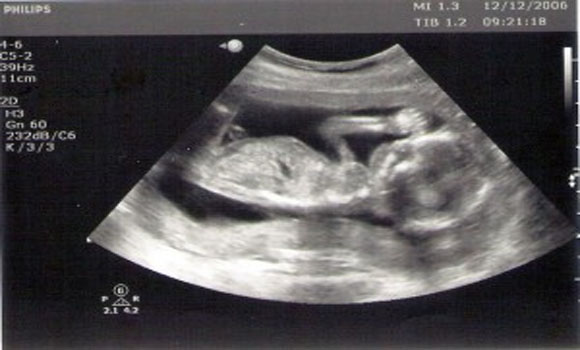

If you had to guess – what would you say is one of the worst things you could do to a developing fetus? Smoking cigarettes? Drinking alcohol? Heavy lifting? Falling down a flight of stairs? Sure – these are all dangerous things to do while pregnant, but another thing that you may not have considered that is actually dangerous to a developing child – ultrasounds!

What do ultrasounds do? Boiled down, they do little more than inform parents about their child’s development and rarely lead to any meaningful action. The only time an ultrasound is actually required is when safety of the child (or mother) is clearly in question and when the results of the test would require action.

Studies published in medical journals Lancet and the Canadian Medical Association Journal show that an ultrasound may affect fetal growth, resulting in babies with lower birth weight. In addition, children are twice as likely to have delayed speech development if they were examined via ultrasound as a fetus.

- Avoid tests that simply provide information. For example, avoid ultrasounds during pregnancy.